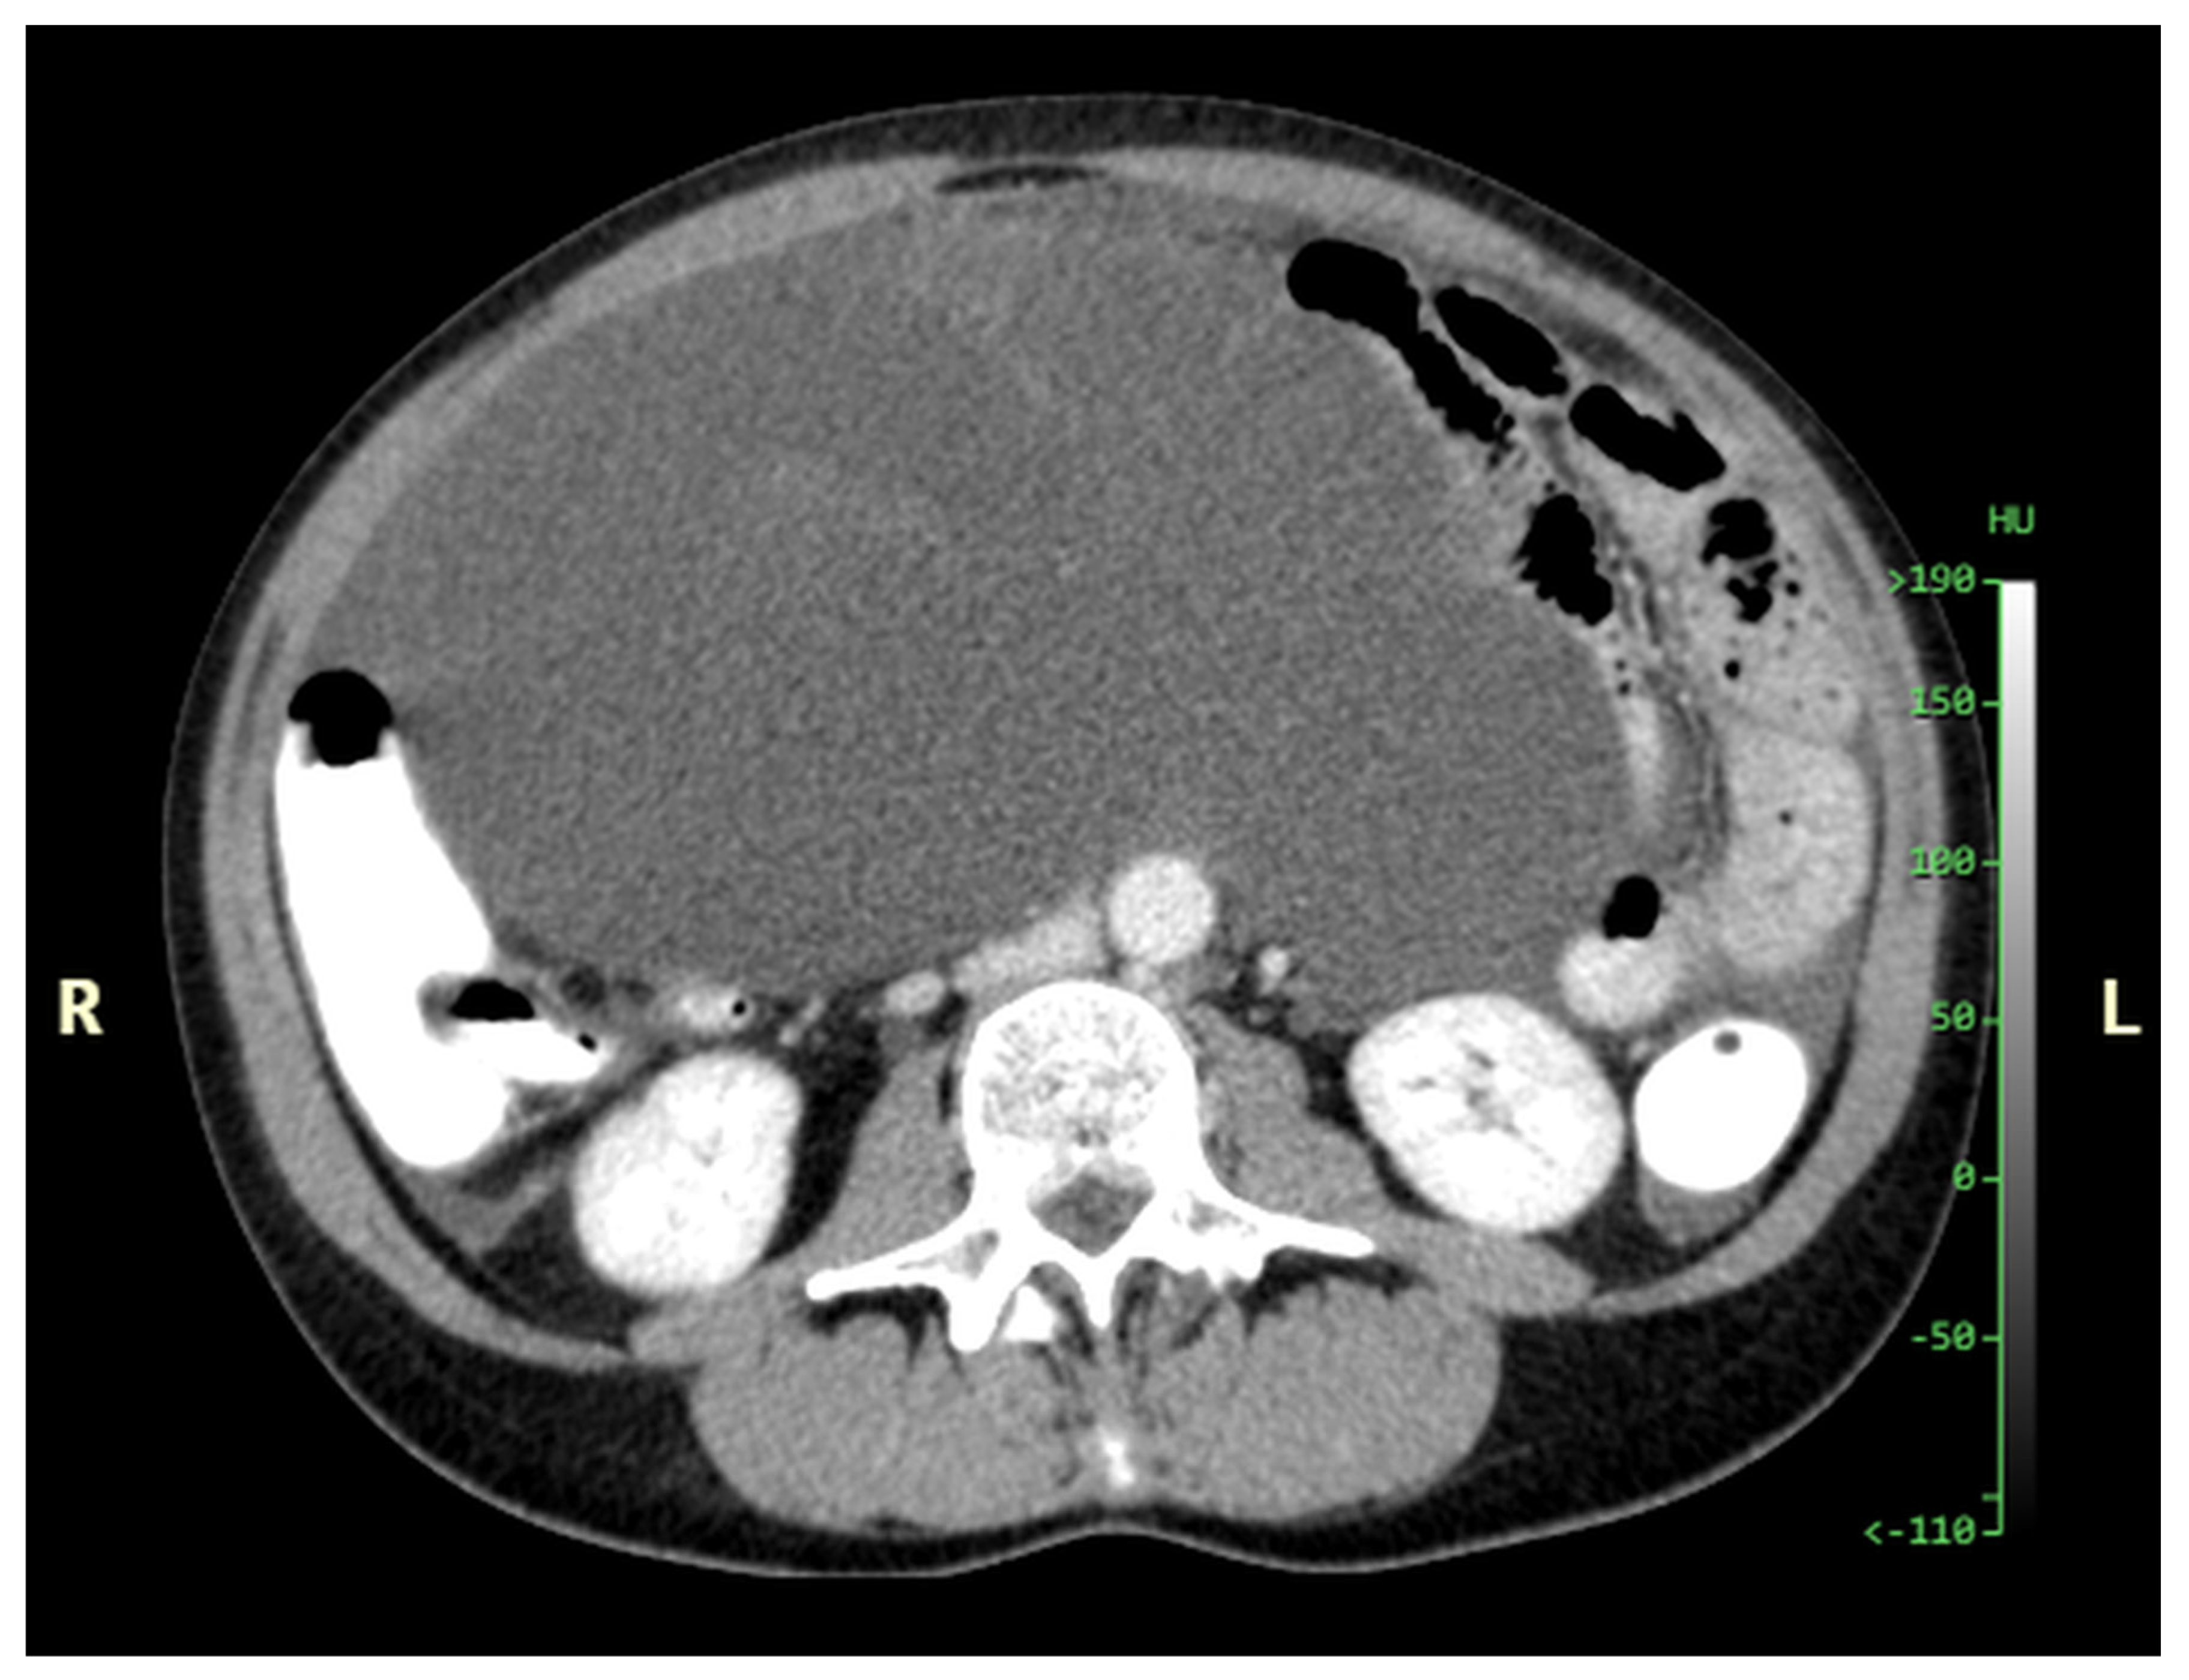

Figure 11, Figure 12, Figure 13, Figure 14 and Figure 15. Advanced stage of the disease. The abdomen is full of tumors and mucin. Typical signs are heterogeneous or hypodense masses in the form of lobules often with septa, which could be enhanced by contrast and could be associated with calcifications.

Patients with a misdiagnosed rupture of the mucocele may develop pseudomyxoma peritonei. It is characterized by the presence of an abundant gelatinous substance in the abdomen. Diffuse, progressive, and abundant mucin-containing tumor cells are typical of this disease [2] (Figure 11, Figure 12, Figure 13, Figure 14, Figure 15 and Figure 16). The interval between rupture and advanced disease is several years. In our clinical series, the interval was about 5 years. In the literature, we found a wide range of this interval from 12 months to 10 years [9,10]. The natural history of PMP revolves around the “redistribution phenomenon”, whereby mucinous tumor cells accumulate in the Douglas pouch, in the diaphragm (more on the right), and the small and large omentum (Figure 17). The small intestine is less involved [4]. Pseudomyxoma peritonei is a slowly progressing disease, which fills the peritoneal cavity over time. There are several classifications of pseudomyxoma. The most commonly used is the PSOGI classification [2]. Mucinous accumulation progresses to malnutrition, bowel obstruction, and respiratory compromise. Rarely, the tumor may spread to the pleural cavity. This has been described in 5.4% of cases. It may occur spontaneously or as a result of diaphragmatic injury during cytoreduction [8,11].

Figure 13. CT, venous phase, axial plane.